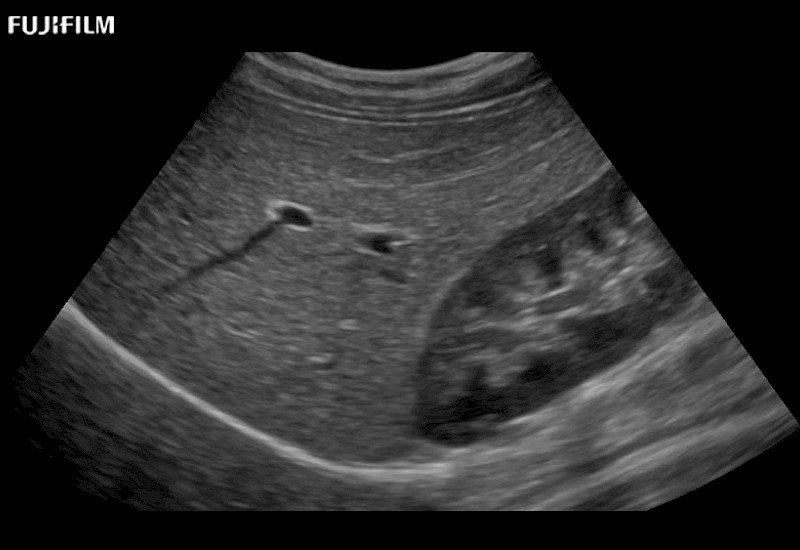

Curved array 4-way laparoscopic transducer for better visualization of targeted lesions.